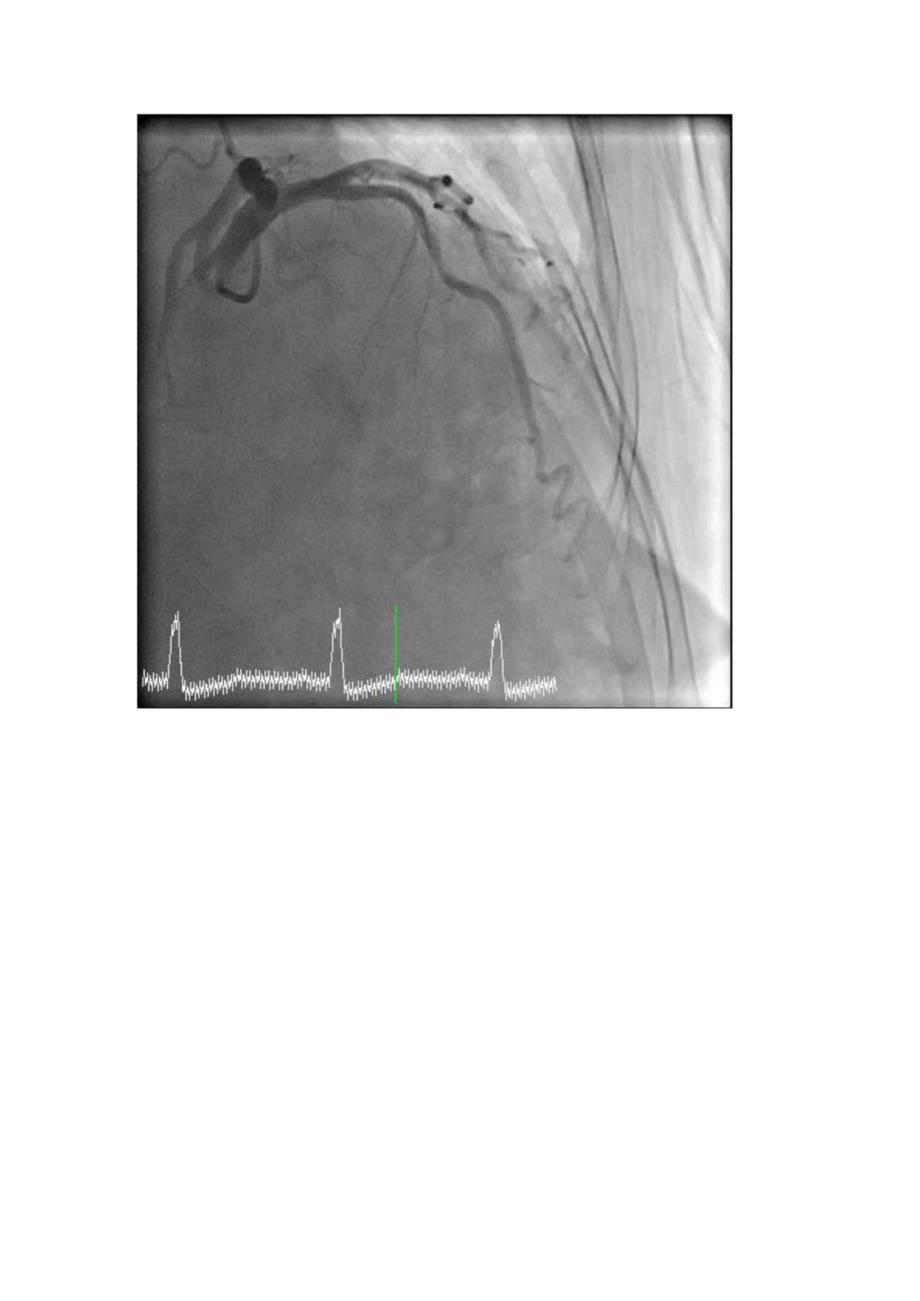

1、病史摘要:1.患者,女,79岁;2 .主诉:反复胸痛不适1月余3 .查体:神清、气平,全身皮肤未见黄染,全身浅表淋巴结未及肿大。双侧瞳孔等大等圆,对光反射存在。口唇无组,伸舌居中,颈软,气管居中,颈静脉无怒张,双侧呼吸音清,双肺未闻及干湿罗音。心率70次/分,律齐,未闻及病理性杂音,血压140/8OnmIHg。腹软,无压痛、无反跳痛。肝脾肋下未及。双下无肢浮肿。正常生理反射存在,病理反射未引出。4 .辅检:20190521于第一人民医院查CK-MB2.lngml,肌红蛋白63.3ngml,肌钙蛋白IV0.05ngml,20190523于我院查心电图示:窦性心律、I度房室传导阻滞、心室内阻滞、V

2、5V6导联ST段近似水平型压低0.5mm,20190623于我院查冠状动脉CT示:左冠前降支中段心肌桥,伴管腔重度狭窄。48小时主治医师诊断:冠心病不稳定心绞痛;高血压3级,很高危;脑梗个人史签名初步诊断:冠心病不稳定心绞痛;高血压3级,很高危;脑梗个人史初步诊断:冠心病不稳定心绞痛;高血压3级,很高危:脑梗个人史动脉造影结果初析:LM:未见明显狭窄,LAD:近中段85%狭窄,狭窄后心肌桥,LCX:优势,未见明显狭窄,RCA:中段管壁不规则。左心室造影:收缩功能可。主动脉根部造影:未见明显异常。介入治疗:对LAD病变血管行PCI。经鞘管插入6F导引导管,经导管送入Sion导丝,2.5*15mm球囊8atm预扩;3.0*2Omm药物球囊8atm扩张30s释放,再造影见残余10%狭窄。退出导管导丝,拔除动脉鞘管,无菌纱布覆盖,安返病房。术后处理详见医嘱。术中血动力学检测:血压:140/7OmmHg,心率:75次/分,主动脉压力:14065mmHg,血氧饱和度:100%。术中情况:患者无胸痛,无手术并发症。术后注意事项:注意患者胸闷胸痛症状,注意术后心电图、心梗三合一等变化,嘱患者静心休息。